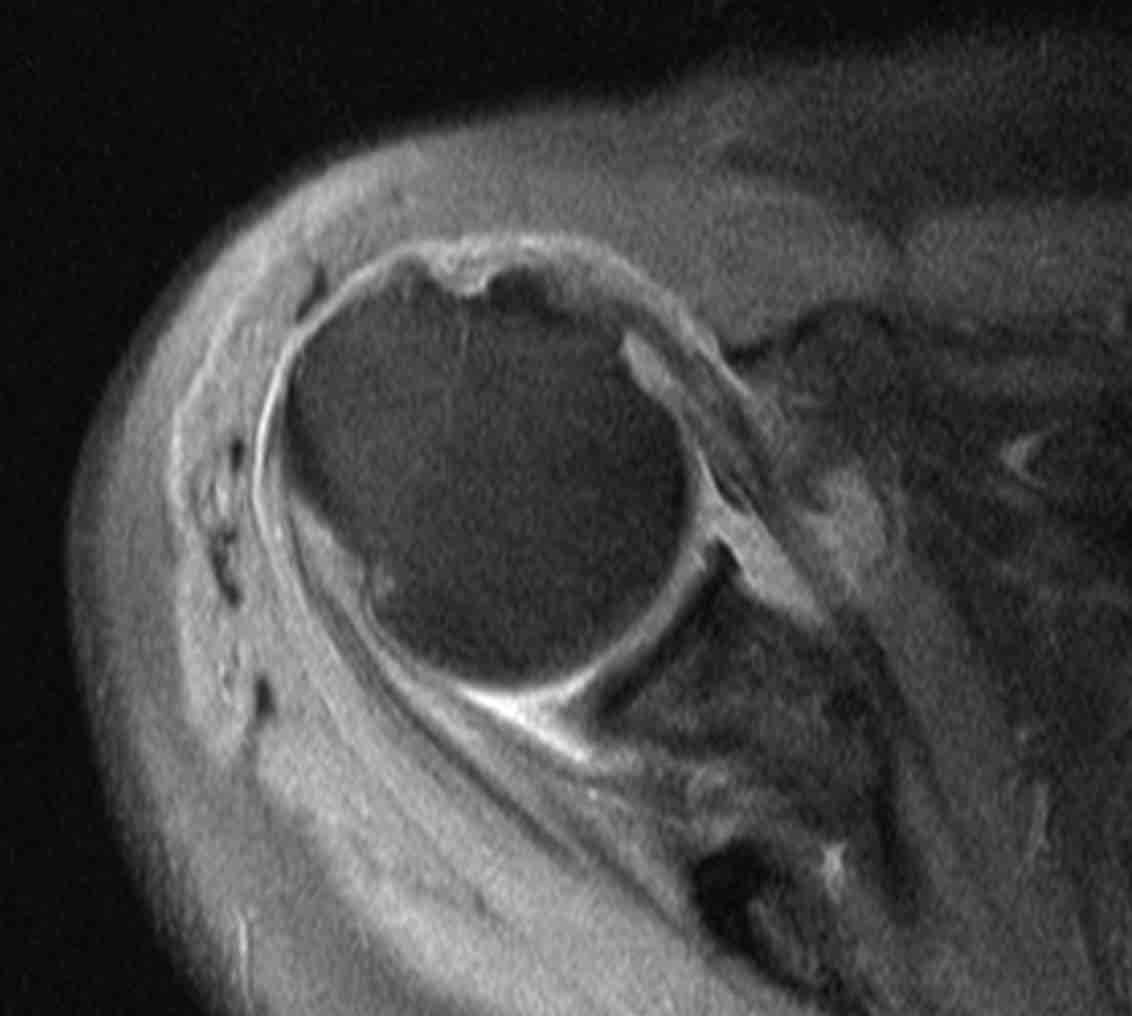

Η έγκαιρη διάγνωση με κλινική εξέταση και απεικονιστικό έλεγχο (υπερηχογράφημα ή μαγνητική τομογραφία) είναι καθοριστική για τη σωστή αντιμετώπιση.

Ο κ. Παναγόπουλος θα λάβει αναλυτικό ιστορικό και θα σας εξετάσει. Μία ακτινογραφία του ώμου θα βοηθήσει να αποκλειστούν άλλα αίτια πόνου, όπως οστεοαρθρίτιδα του ώμου ή ασβεστοποιός τενοντίτιδα. Ο κ. Παναγόπουλος θα σας υποβάλλει σε υπερηχογράφημα ώμου, για να επιβεβαιώσει την παρουσία ρήξεων στο στροφικό πέταλο. Σε ορισμένες περιπτώσεις, ο ιατρός θα σας παραπέμψει για μαγνητική τομογραφία για την αξιολόγηση του μεγέθους της ρήξης ή τυχόν ατροφίας των μυών.

- Η διάγνωση γίνεται με κλινική εξέταση και μαγνητική τομογραφία ή υπερηχογράφημα.